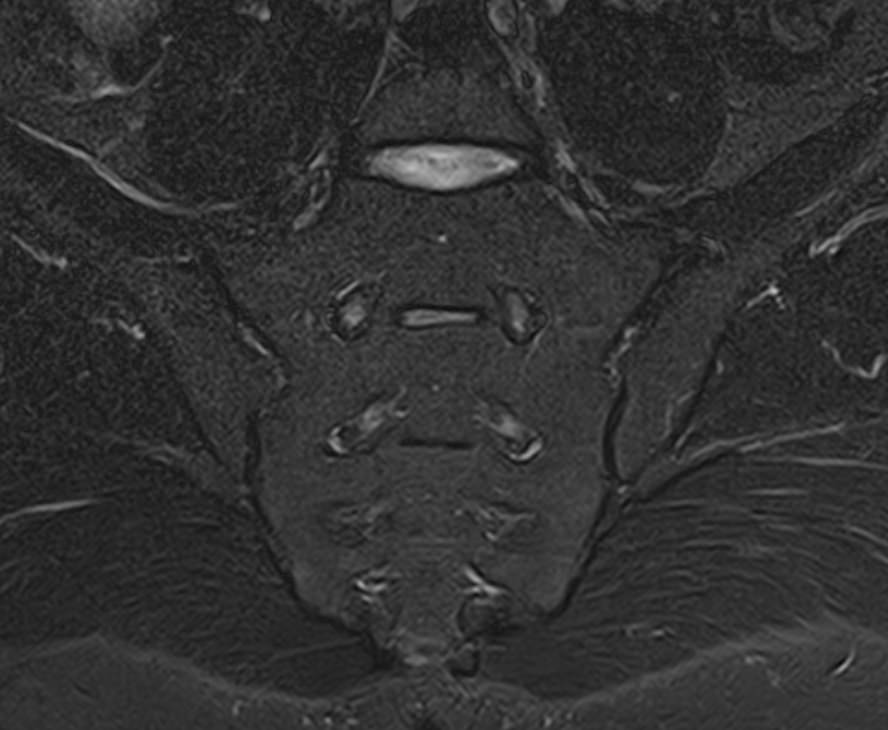

Наиболее точным и эффективным способом диагностики причин появления болей в нижней части спины является МРТ. С помощью данного метода можно оценить состояние всех анатомических структур позвоночного столба на исследуемом уровне, диагностировать поражение позвоночника на начальной стадии, когда другие методы не дают результатов. Такой патологией, в частности, является сакроилеит (воспаление крестцово-подвздошного сочленения), который часто становится причиной анкилоза (сращения) или нестабильности (патологической подвижности) сустава. Выявление сакроилеита на ранней стадии значительно улучшает прогноз в плане лечения и профилактики осложнений.

В клинике «Доступная медицина» диагностика патологии нижней части спины осуществляется на высокотехнологичном оборудовании – новейшем высокопольном томографе TOSHIBA VANTAGE TITAN 1,5 Тесла, который обеспечивает высочайшее качество изображений, точность и достоверность полученных данных. Магнитно-резонансная томография осуществляется без применения ионизирующего излучения, поэтому является безопасным методом обследования и может применяться неоднократно по мере необходимости.

Что можно диагностировать при проведении МРТ пояснично-крестцового отдела позвоночника + МРТ крестцово-подвздошных сочленений

При проведении данного комплексного обследования можно выявить:

• дегенеративно-дистрофические заболевания позвоночника: спондилез, спондилоартроз, остеохондроз;

• стеноз (сужение) позвоночного канала;

• грыжи межпозвонковых дисков (протрузии, экструзии);

• переломы позвонков, их смещение;

• спондилиты, гнойные артриты, сакроилеит, абсцессы околопозвоночных тканей и другие воспалительные заболевания, туберкулез;

• опухоли позвоночника и окружающих тканей;

• патологические изгибы позвоночника, сколиоз, усиленный или выпрямленный лордоз как нарушение статической функции позвоночника;

• аномалии строении позвоночника.